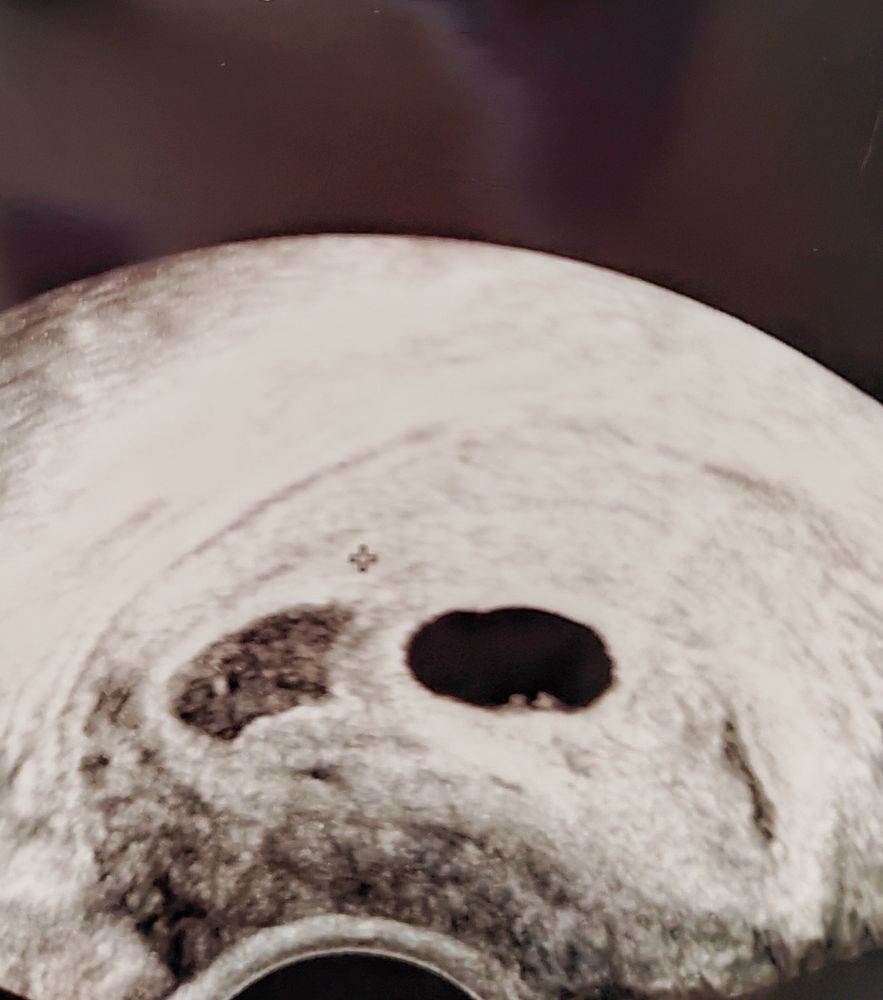

Хотелось бы услышать ваше мнение. Последнии месячные 05.11. Продолжительность 5 дней. Колебания длины цикла 23-28 дней. На предпоследнем узи поставили под вопросом замершую беременность (фото узи приложу). На следующий день в другой клинике сказали, что плодное яйцо выросло сильно и она не сказала бы что она замершая, такое ощущение он к стенке прижат (фото узи также приложу). Может ли это быть замершая беременность с учётом того, что срок по месячным 7 недель. По сроку зачатия 5-6 недель.

Раз плоднле яйцо пустое это значит анэбриония.., у меня на таком сроке два раза было , ПЯ может расти но увы без эмбриона

у меня в плодном яйце 14 мм еще не было видно эмбриона. Но был виден ЖМ. Мне кажется нужно подождать еще немного и понаблюдать.

Кошка В Сапожках, Было 4.8 мм. Сейчас 11 мм. За неделю выросло на 6.2 мм

Yana Pepper, у меня эмбрион 2 мм был виден в пя 18 мм. Мне кажется, есть смысл подождать немного и переделать УЗИ.

Yana Pepper, ну в любом случае подождать. Анэмбрионию ставят при отсутствии эмбриона в ПЯ размером 25 и более мм. Раз ПЯ растет, то динамика есть, а вот какая она будет дальше только время покажет